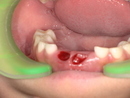

10代男性 横に生えた状態で埋まっていた親知らずを抜いて「智歯周囲炎」を改善した症例

名古屋 市 天白区の歯医者・歯科・親知らずの抜歯治療・歯科口腔外科のイナグマ歯科です。院長 ...